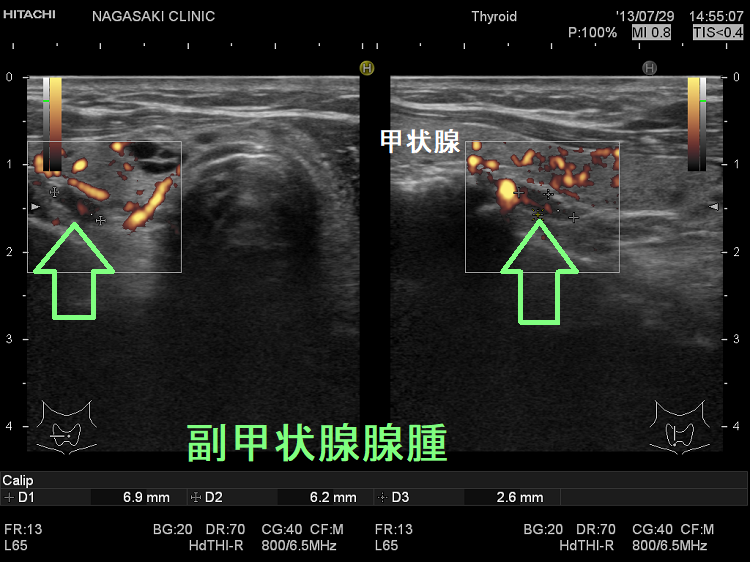

(➸)原因となる副甲状腺腺腫、副甲状腺癌、副甲状腺過形成をデジタルハイビジョン超音波診断装置で診断。エコーでは、甲状腺とのインピーダンスの違いにより、甲状腺-副甲状腺境界部に線状高エコーが生じます(右図の↓)。内部は中心血流を認め、リンパ節でないのが分かります。

微小副甲状腺腫;血清カルシウムは正常範囲内の上限だが、脱水などの影響で上限を超える場合もある。骨密度は正常で、腎結石(腎臓結石)もない。